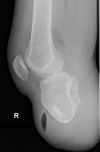

Unusual appearance of air in soft tissue on ultrasound